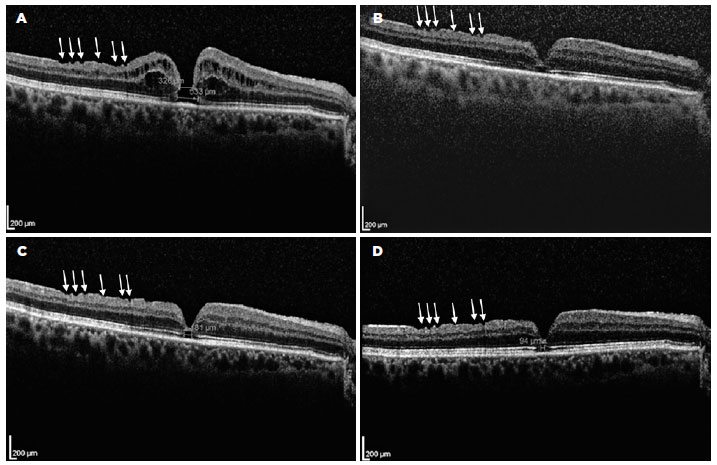

A 68-year-old man who had undergone combined cataract and iFTMH surgery in his right eye (OD) 15 months before at another institution presented at our outpatient clinic for routine examination. The best-corrected visual acuity (BCVA) in OD was counting fingers, with pseudophakia and normal intraocular pressure. Fundus examination evidenced an iFTMH in the right eye; the left eye showed no abnormal findings. The patient’s presurgical spectral domain optical coherence tomography (SD-OCT) study demonstrated a FTMH, but the iFTMH was not measured (Figure 1). A new SD-OCT scan revealed the persistence of the iFTMH, with 326 and 533 microns of mid- and base-hole diameters, respectively (Figure 2A). A new surgery was offered, but the patient declined. Thus, he was set for follow-up every 6 months.

Twenty-one months after his first consultation with us (36 months after the surgery), the BCVA in the right eye had improved to 20/200. Slit-lamp examination revealed posterior capsule opacification while fundus examination and SD-OCT revealed the spontaneous closure of the iFTMH (Figure 2B), with a gap at the foveal ellipsoid zone (EZ).

Twelve months after the verified closure of the iFTMH, posterior capsulotomy was performed, and the BCVA improved to 20/30. At the final visit, 22 months after the closure of the iFTMH, the patient’s BCVA was 20/25, and the gap at the EZ diminished its diameter from 181 microns (Figure 2C) to 94 microns (Figure 2D).

A pre-existing iFTMH was the primary reason for the surgery in our patient. We did not have access to the preoperative clinical records, but ILM peeling was assumed to be performed owing to the presence of superficial focal retinal depressions known as inner retinal dimples (Figure 2, white arrows), which are supposed to be due to diffuse loss of the Müller cell end-feet and whose presence is considered a late sign of an already peeled ILM(10). The preoperative SD-OCT study result brought to us by the patient was from another clinic, and unfortunately, the iFTMH was not measured. Thus, the presurgical and postsurgical iFTMH sizes could not be compared.